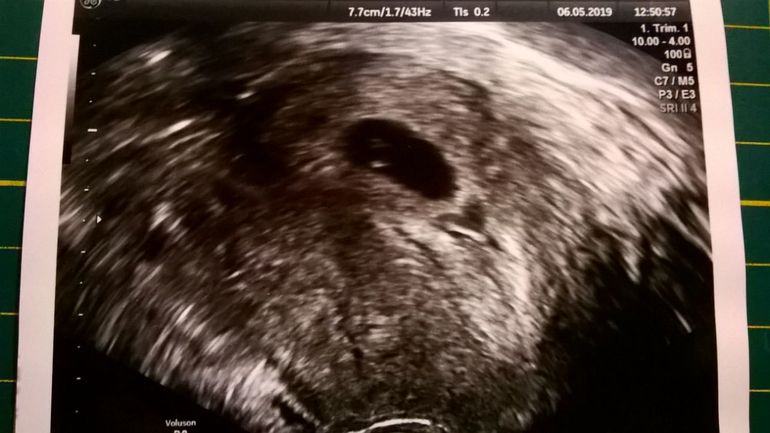

И вот тут-то начинается мой сумбур. Сразу скажу, что врач сказал, что у меня беременность маточная и всё хорошо. Срок поставил 6 недель и 3 дня. Видимо, он считает срок по-другому, чем я.

Сказал, что сердцебиение рано смотреть, так как всего 6 недель и мерить эмбрион по той же причины рано.

Узи сделал, взял мазок, дал снимок и отправил домой на 2 недели.